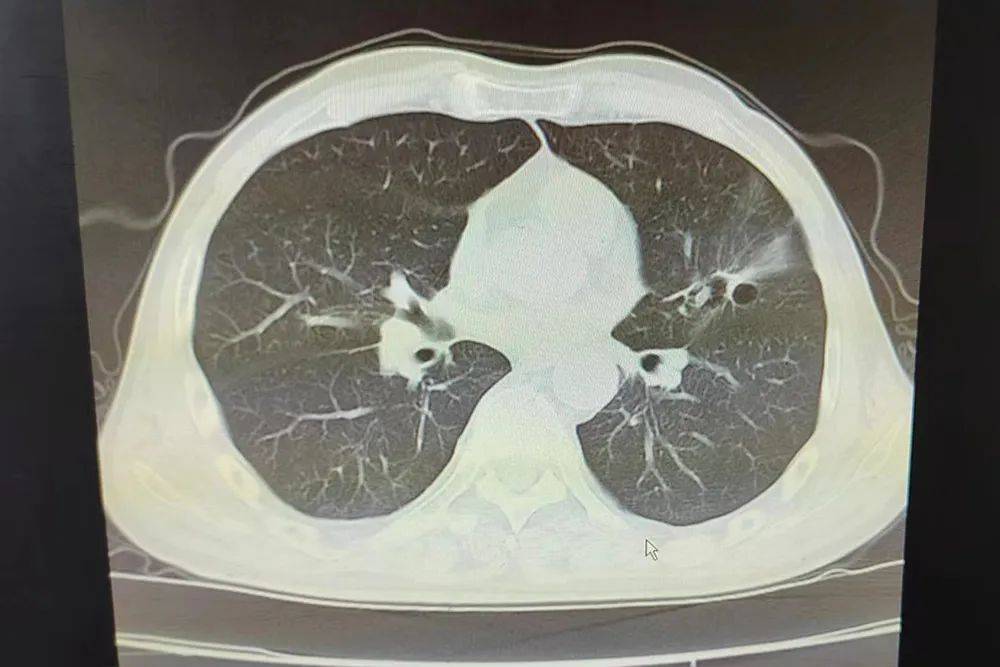

建华肿瘤一科微创治疗肺癌病例分享

图片尺寸4032x3024